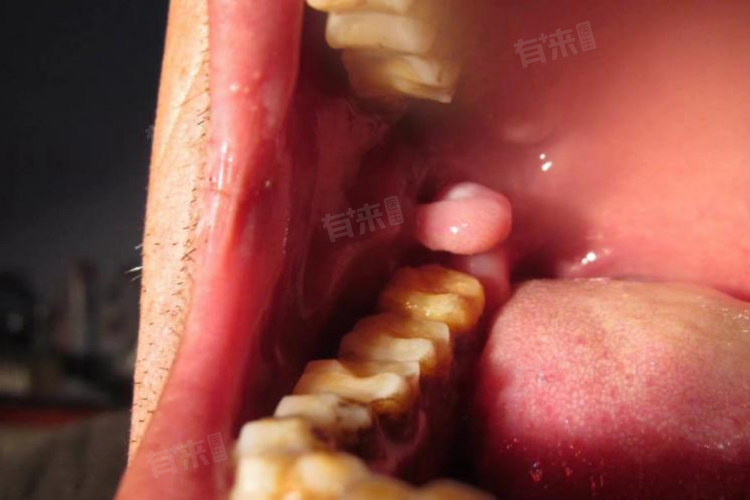

口腔内壁有坨肉鼓起来可能是由多种原因引起的,包括口腔溃疡、口腔感染、黏液腺囊肿、口腔肿瘤等。建议及时前往医院口腔科就诊,以便专业医生根据具体情况进行诊断和治疗。

3、黏液腺囊肿:

黏液腺囊肿也是导致口腔内壁肉坨凸起的常见原因,当黏液腺排泄管受阻,腺体内的分泌物潴留于腺泡内时,就会使腺泡逐渐膨胀而形成肉状凸起、囊肿。对于黏液腺囊肿,根据囊肿的大小和位置,可能需要进行手术切除。